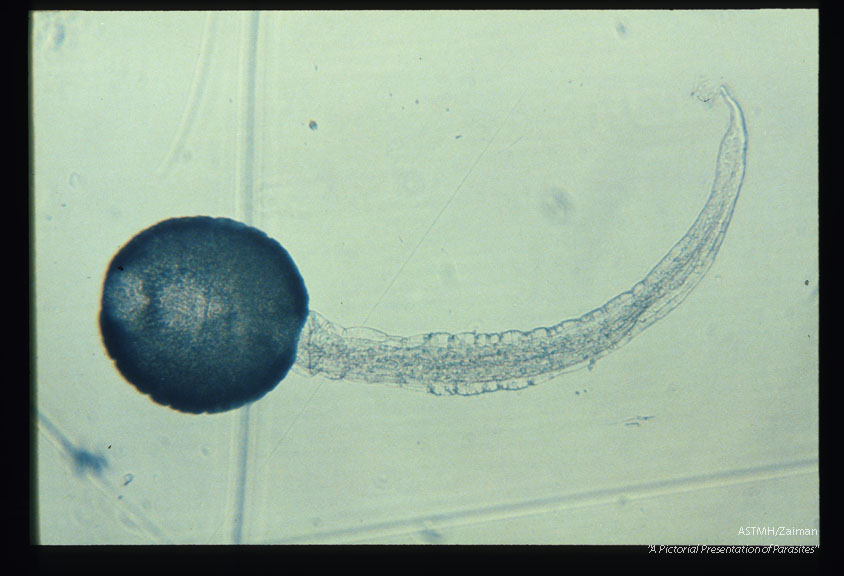

Cercaria.

Fasciola hepatica

Description: Cercaria.